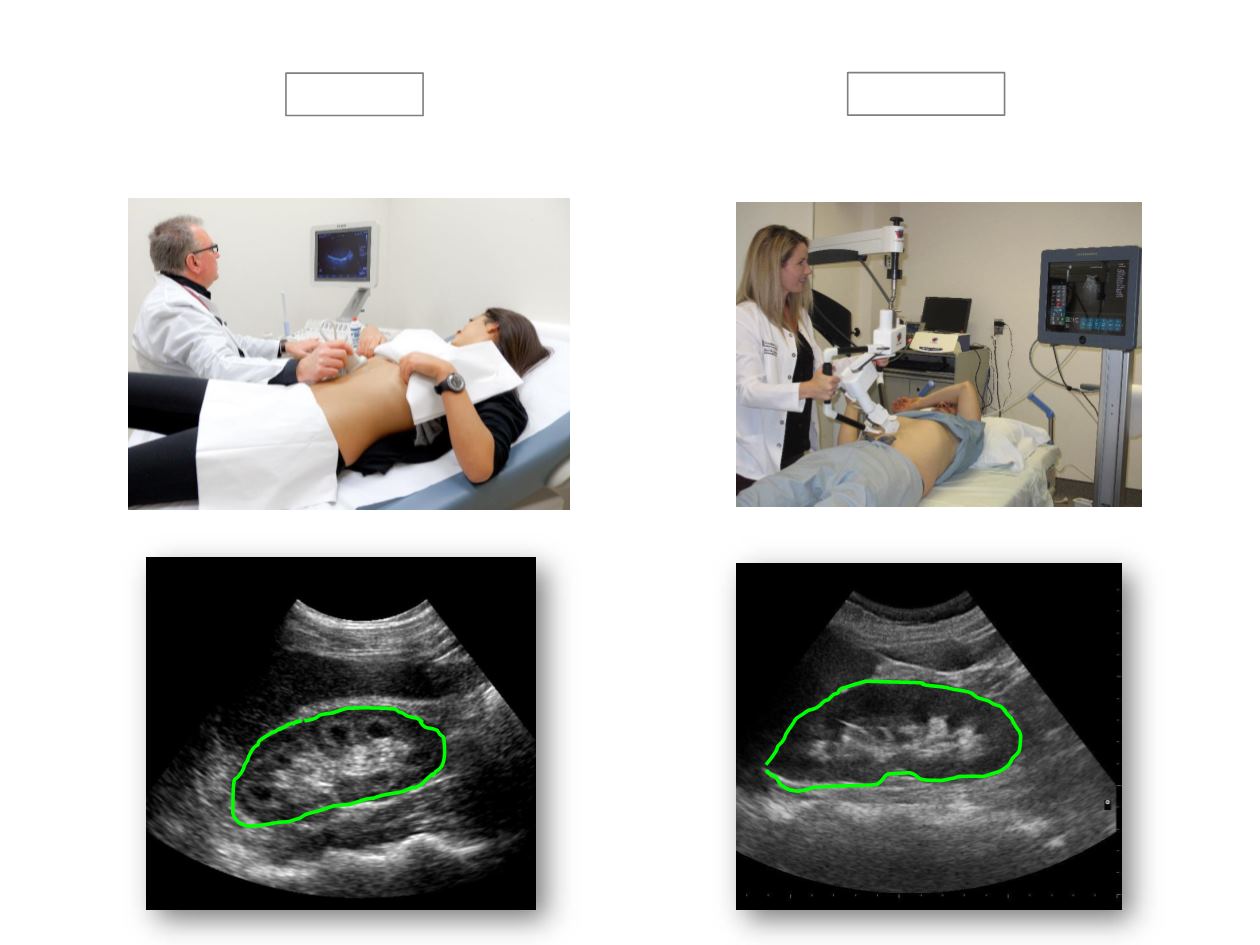

DIRECT U/S

REMOTE U/S